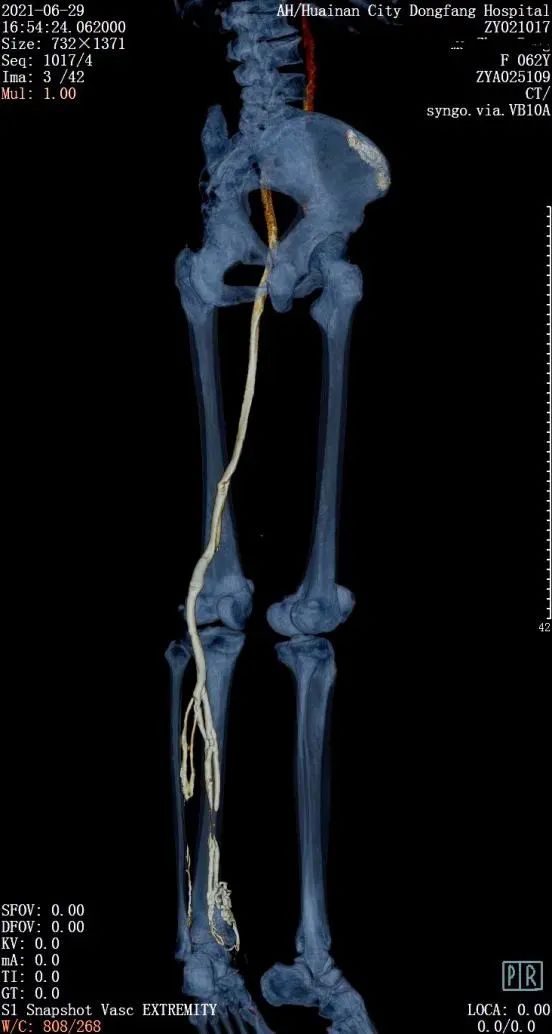

淮南东方医院集团影像中心和血管外科为了攻破此项技术,多次开展相关业务知识学习和培训,查阅大量前沿的文献资料,借鉴国内外成功检查经验,积极开展技术储备。近日,集团影像中心陈忠主任带领团队,在严格制定好技术参数、检查流程和应急预案的前提下,护理组、技术组、诊断组三个部门密切配合,在双源CT机器下完成三例下肢静脉CTA检查,检查过程顺利,图像质量满意,标志着该项技术已经正式应用于临床。

相较于以前的检查技术,螺旋CT下肢静脉造影检查技术(下肢静脉CTV)具备更多的优势:检查范围大,时间短,可以多角度显示下肢静脉血管病变的部位及范围,图像更为直观,而且具有微创、可重复等特点,扫描结束后利用数据进行二维和三维重建,观察血管腔内的病变情况,排查血管腔内有无血栓,术前评估下肢深浅静脉组的沟通情况,了解栓子形态及管腔狭窄情况,判断狭窄原因是腔内阻塞还是腔外压迫,还可以寻找血管损伤出血的部位,指导临床一线精准治疗。